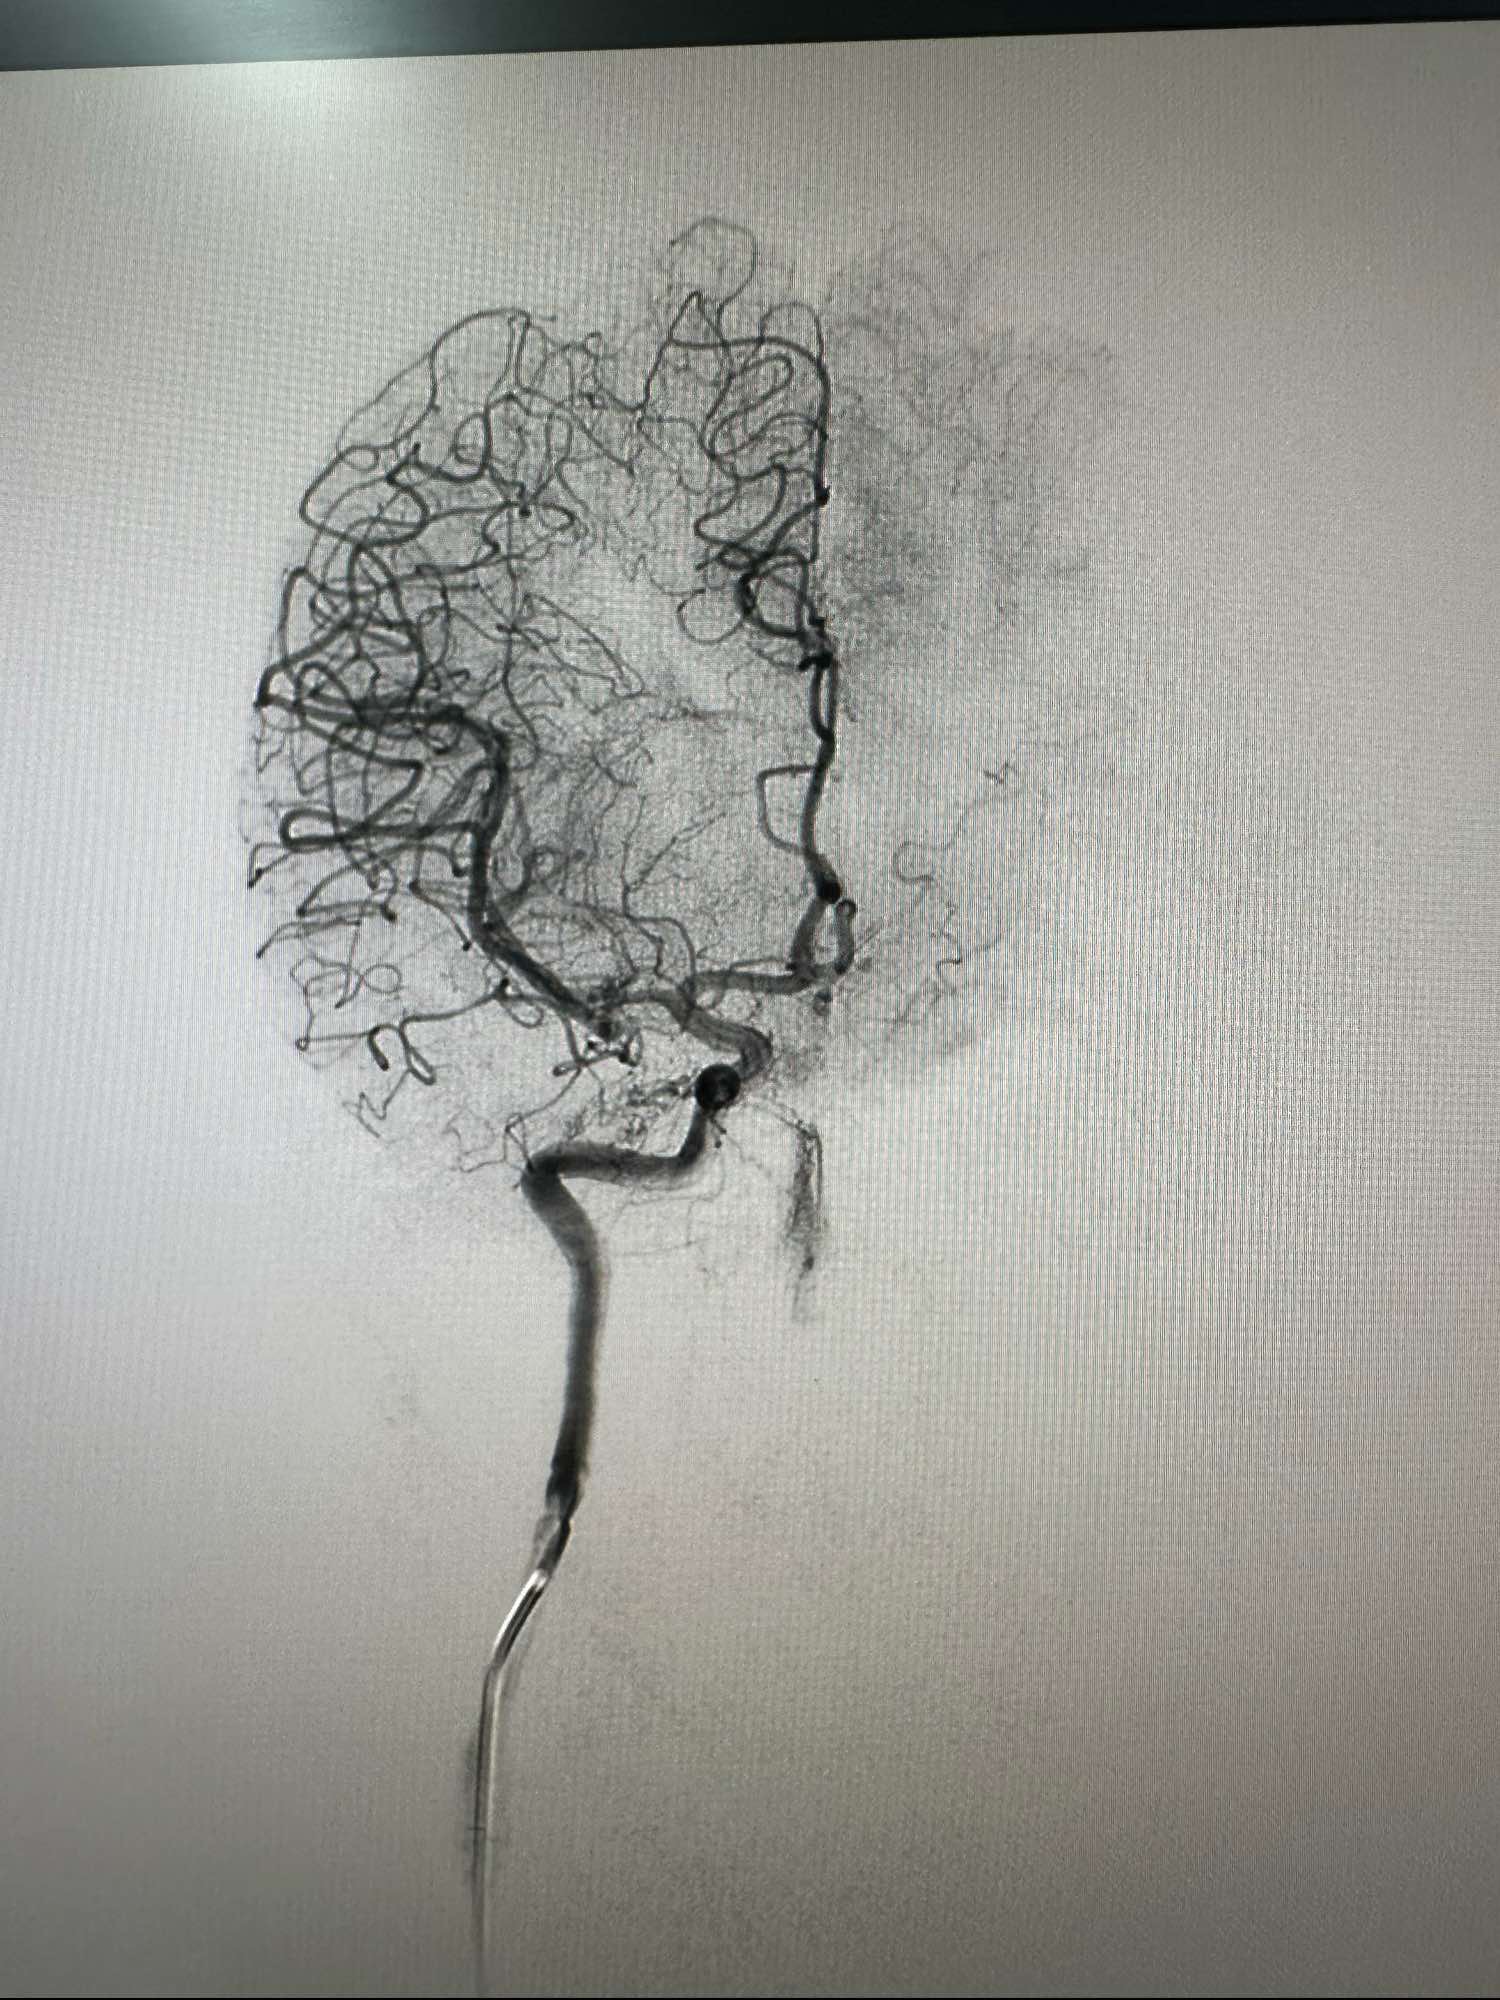

左侧颈内动脉术前3D图像

另外一个角度,动脉瘤大小约3mm左右,宽颈

另外一个角度